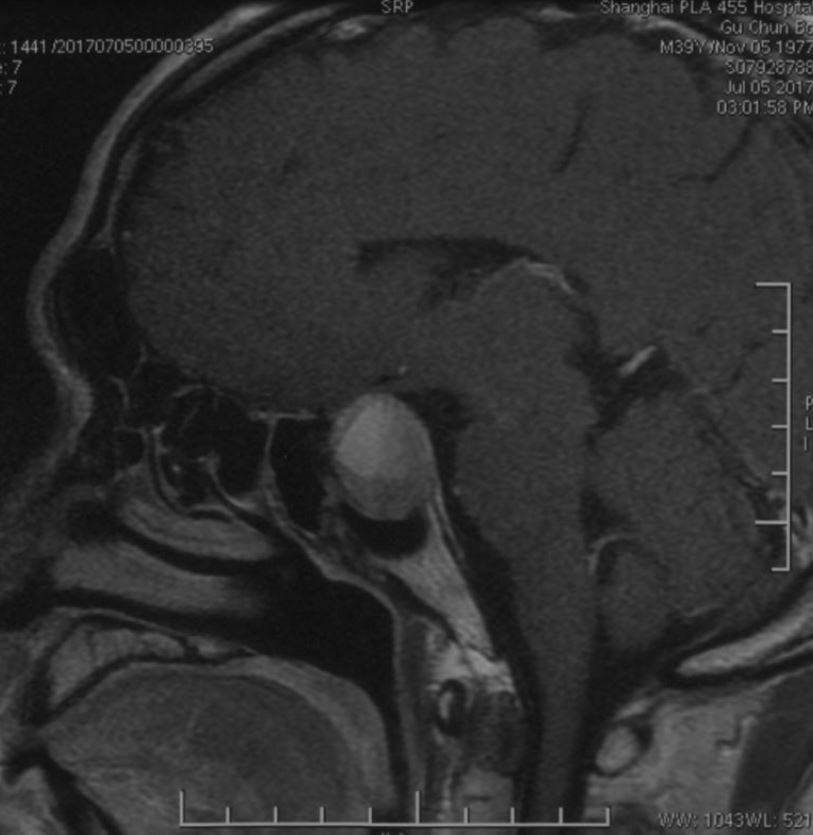

鞍区磁共振检查发现:鞍区肿瘤卒中可能,肿瘤侵犯双侧海绵窦、颈内动脉,鞍隔被顶起,鞍底部分塌陷。复旦大学附属肿瘤医院神经外科高阳

TIWI像